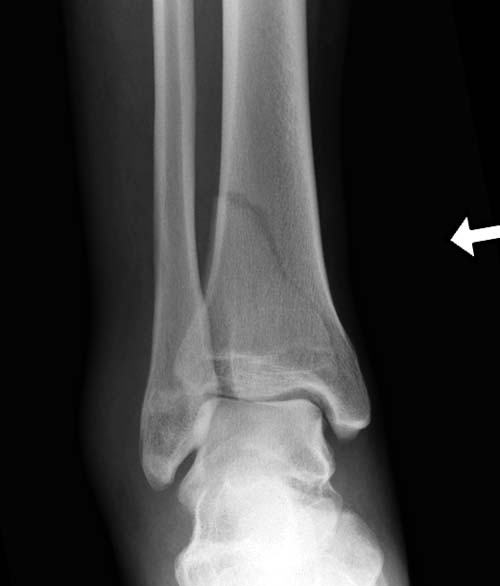

Первый случай, где перелом в результате падения с небольшой высоты, где мортиз рентген снимок показал отстутствие укорочения наружной

лодыжки и КТ срезы подсказали направления атаки. После такой фиксации нет надобности в гипсовой повязке, брейс и через две недели движения в

суставе без нагрузки.